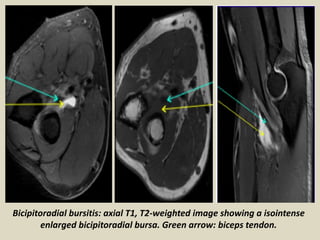

Bicipitoradial bursitis: axial T1, T2-weighted image showing a isointense

enlarged bicipitoradial bursa. Green arrow: biceps tendon.